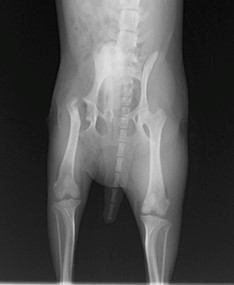

眼球摘出、眼瞼腫瘤切除、チェリーアイ整復、眼瞼縫合、瞬膜フラップ、眼球突出整復、耳介切除、垂直耳道切除、総耳道切除、鼻鏡切除、口腔腫瘍切除(上顎骨切除、下顎骨切除を含む)、各種抜歯(猫の全臼歯抜歯含む)舌腫瘍切除、唾液腺嚢胞切除、皮膚腫瘤切除、断脚(前肢、後肢、片側骨盤切除)、断尾、肺葉切除、胸腺腫切除、心膜切除、横隔膜ヘルニア整復、肝臓腫瘍切除、胆嚢摘出、胃切開、胃拡張胃捻転症候群整復、胃腫瘍切除、腸管切開、腸管腫瘍切除、直腸腫瘍切除(粘膜、全層プルスルーなど)、腎臓摘出、SUB設置手術、脾臓摘出、副腎摘出、膀胱切開、膀胱腫瘍切除(部分切除、全摘出、膀胱尿道一括切除など)、卵巣腫瘍切除、精巣腫瘍切除、卵巣子宮全摘出、肛門嚢切除、各種骨折、膝蓋骨脱臼整復、股関節脱臼整復、大腿骨頭切除、椎間板ヘルニア(各種椎弓切除術)、各種リンパ節切除 など